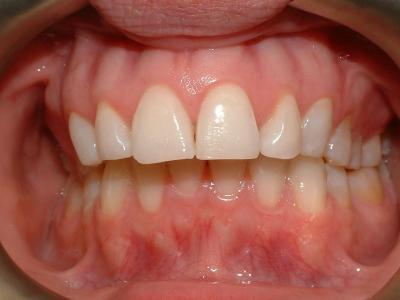

Изменение прикуса, расходятся нижняя и верхняя челюсти

Чаще всего после удаления восьмёрки остальные зубы начинают «расходиться» и «раздвигаться», что приводит к изменению прикуса.

Если деформация прикуса происходит после удаления верхних восьмёрок, это можно определить по следующим симптомам:

- нижняя челюсть выпирает вперёд;

- между верхними зубами увеличивается пространство;

- верхние клыки не совпадают с нижними при смыкании зубов;

- отсутствует возможность комфортно закрыть рот.

Деформация прикуса при удалении нижних восьмёрок проявляется следующим образом:

- чрезмерное выдвижение вперёд верхней челюсти;

- увеличение пространства между нижними зубами;

- при пережёвывании пищи появляется дискомфорт из-за того, что моляры и премоляры не могут правильно сомкнуться;

- нижние клыки не совпадают с верхними.